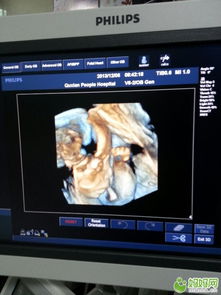

22周系统彩超,又称为大排畸检查,是孕期产前检查中非常重要的一环。这一阶段的胎儿已经发育到一定程度,器官结构基本成形,通过系统彩超可以全面了解胎儿的生长发育情况,及时发现胎儿畸形、染色体异常等问题。

胎儿解剖结构检查:观察胎头、颜面部、颈部、胸部、心脏、腹部、脊柱、四肢等部位,检查是否存在畸形。